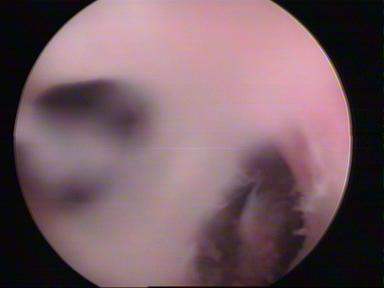

Septate Uterus Lap

Septum Resection

Septum UterusDIAGNOSTIC LAPAROSCOPY

Operative hysteroscopy can treat many of the abnormalities found during diagnostic hysteroscopy. Operative hysteroscopy is similar to diagnostic hysteroscopy except that narrow instruments are placed into the uterine cavity through a channel in the operative hysteroscope. Fibroids, scar tissue, and polyps can be removed from inside the uterus. Some structural abnormalities, such as a uterine septum, may be corrected through the hysteroscope.